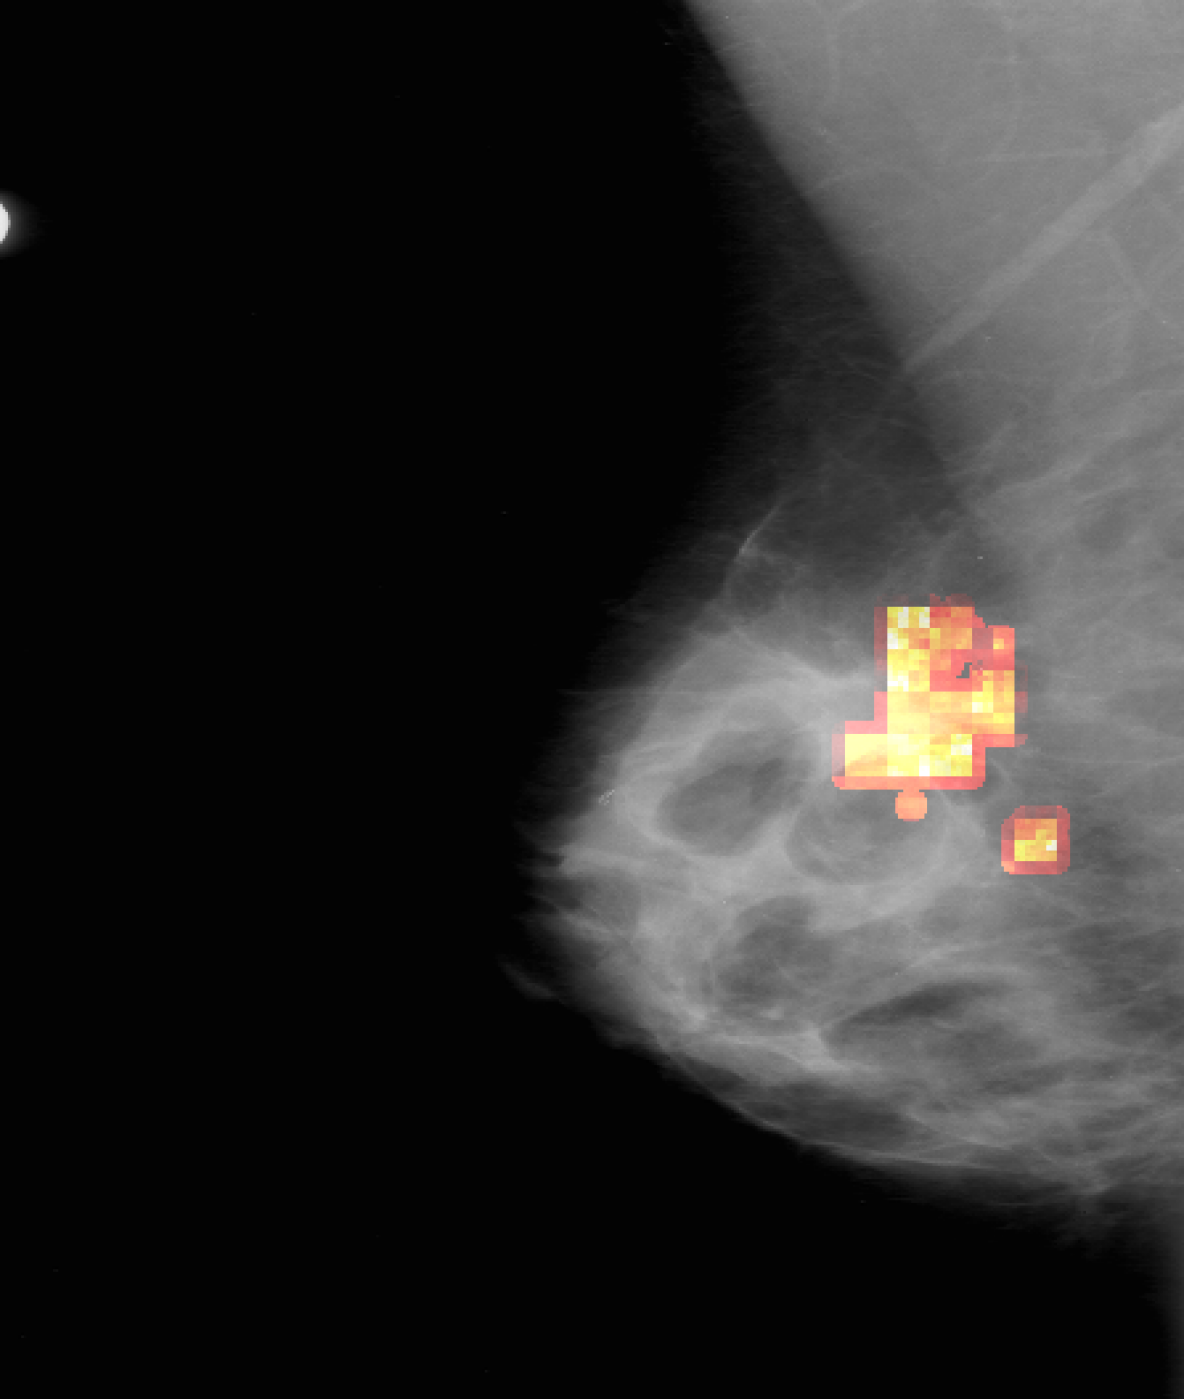

Figure 3: Result attribution heatmaps for mammography [17] and chest X-ray [14]: (a) original image overlayed with annotation contours (and arrows for missing GT), (b) our attribution framework. (c) GradCAM [25] (d) Saliency [26].

Attribution: We compared our attribution network against the gradient explanation saliency map [26] (SAL), and the network/gradient-derived GradCAM [25] visualizations. We limited our comparisons to these direct approaches, as they are widely used within medical imaging [13], and inherently valid [2]. Popular reference based approaches either utilize blurring, noise or some other heuristic [9, 8, 31], or were not available [7], therefore could not be considered. Quantitatively, we relate (i) the result-maps M^^𝑀\hat{M} to both organ, and ground truth (GT) annotations, and (ii) to each other. Particularly for (i) we studied the Hausdorff distances H𝐻H between GT and M^^𝑀\hat{M} indicating location proximity. Lower values demonstrate better localization in respect to the pathology. Further, we performed a weak localization experiment [8, 9]: per image, we derived bounding boxes (BB) for each connected component of GT and M^^𝑀\hat{M} attributions. A GT BB counts as found, if any M^^𝑀\hat{M} BB has an IOU 0.125absent0.125\leq 0.125. We chose this threshold, as a proficient classifier presumably focuses on the masses’ boundaries and neighborhoods, thereby limiting possible BB-overlap. We report average localization L𝐿L. For (ii) we derived the area ratio A𝐴A between M^^𝑀\hat{M} and organ-mask (breast-area) or whole image (chest X-ray). Again, lower values indicate a smaller thereby clearer map. Due to missing GT we could only derive (ii) for TBC. All measurements were performed on binary masks, hence GradCAM and SAL had to be thresholded. We chose the 50,75,9050759050,75,90 percentiles, i.e. compared 50,25,1050251050,25,10 percent of the map-points. Where multiple pathologies, or mapping results occurred we used the median for a robust estimation per image. Statistically significant difference between all resulting findings was formalized using Wilcoxon signed-rank tests, for α<0.05𝛼0.05\alpha<0.05. Additionally we followed [2], and tested our network with randomised parametrization (labels have no effect in our case).

As seen in Table 1, our framework achieves significantly lower H𝐻H, than either GradCAM or SAL at all threshold levels. Moreover, we report significantly better weak localization (L𝐿L) which underlines the higher accuracy of our approach. Qualitatively our attribution-maps are tighter focused (c.f. Fig. 3(b)) and enclose the masses. The former is also expressed by the lower overlap values A𝐴A. All p-values where significantly below 1e-21e-21\text{e-}2, hardening our results. Randomization of the ANN’s weights yields pure noise maps, hence we pass [2]’s checks.